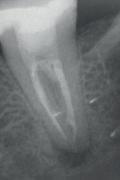

tiële wortelkanaalbehandeling uitgevoerd. Na het lokaliseren van de twee distale en de twee mesiale kanalen, viel het op dat in het mesiolinguale kanaal een restant pulpaweefsel bleef ‘hangen’ nadat het element zorgvuldig was gespoeld. Verdere exploratie leerde dat hier sprake was van een mid-mesiaal wortelkanaal. In totaal werden in deze casus dus 5 wortelkanalen gevonden!

Afbeelding 4. Het viel op dat in het mesiolinguale kanaal een restant pulpaweefsel bleef ‘hangen’ nadat het element zorgvuldig was gespoeld. Verdere exploratie leerde dat er hier sprake was van een mid-mesiaal wortelkanaal. Op de foto is fraai te zien dat het echt om twee aparte kanalen gaat.

Afbeelding 5. In totaal worden er in dit gebitselement dus 5 wortelkanalen gevonden. Waarschijnlijk zijn er nog talloze anastomoses, maar die moeten we schoonkrijgen door een goed spoelprotocol.